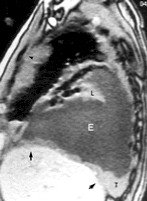

RMN DE CORTE SAGITAL EN LA QUE SE OBSERVA UNA INVASION DE LA PARED TORACICA, TUMOR ( LETRA T), DERRAME PLEURAL (LETRA E), PULMON COLAPSADO (LETRA L) Y COMPROMISO HEPATICO (FLECHAS NEGRAS)